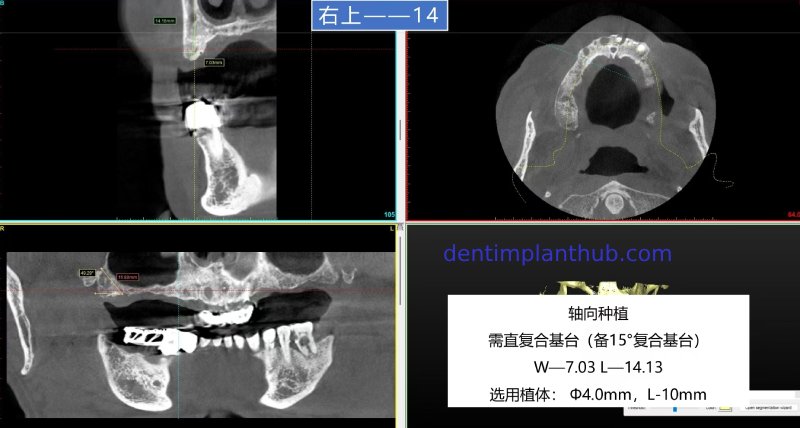

The specific conditions of each tooth position and the implant plan

For tooth 14, with a width of 7.03 and a height of 14.13, an implant with a diameter of 4 and a length of 10 is selected. It will be implanted axially. A straight composite abutment is required, with a 15° composite abutment as a backup.